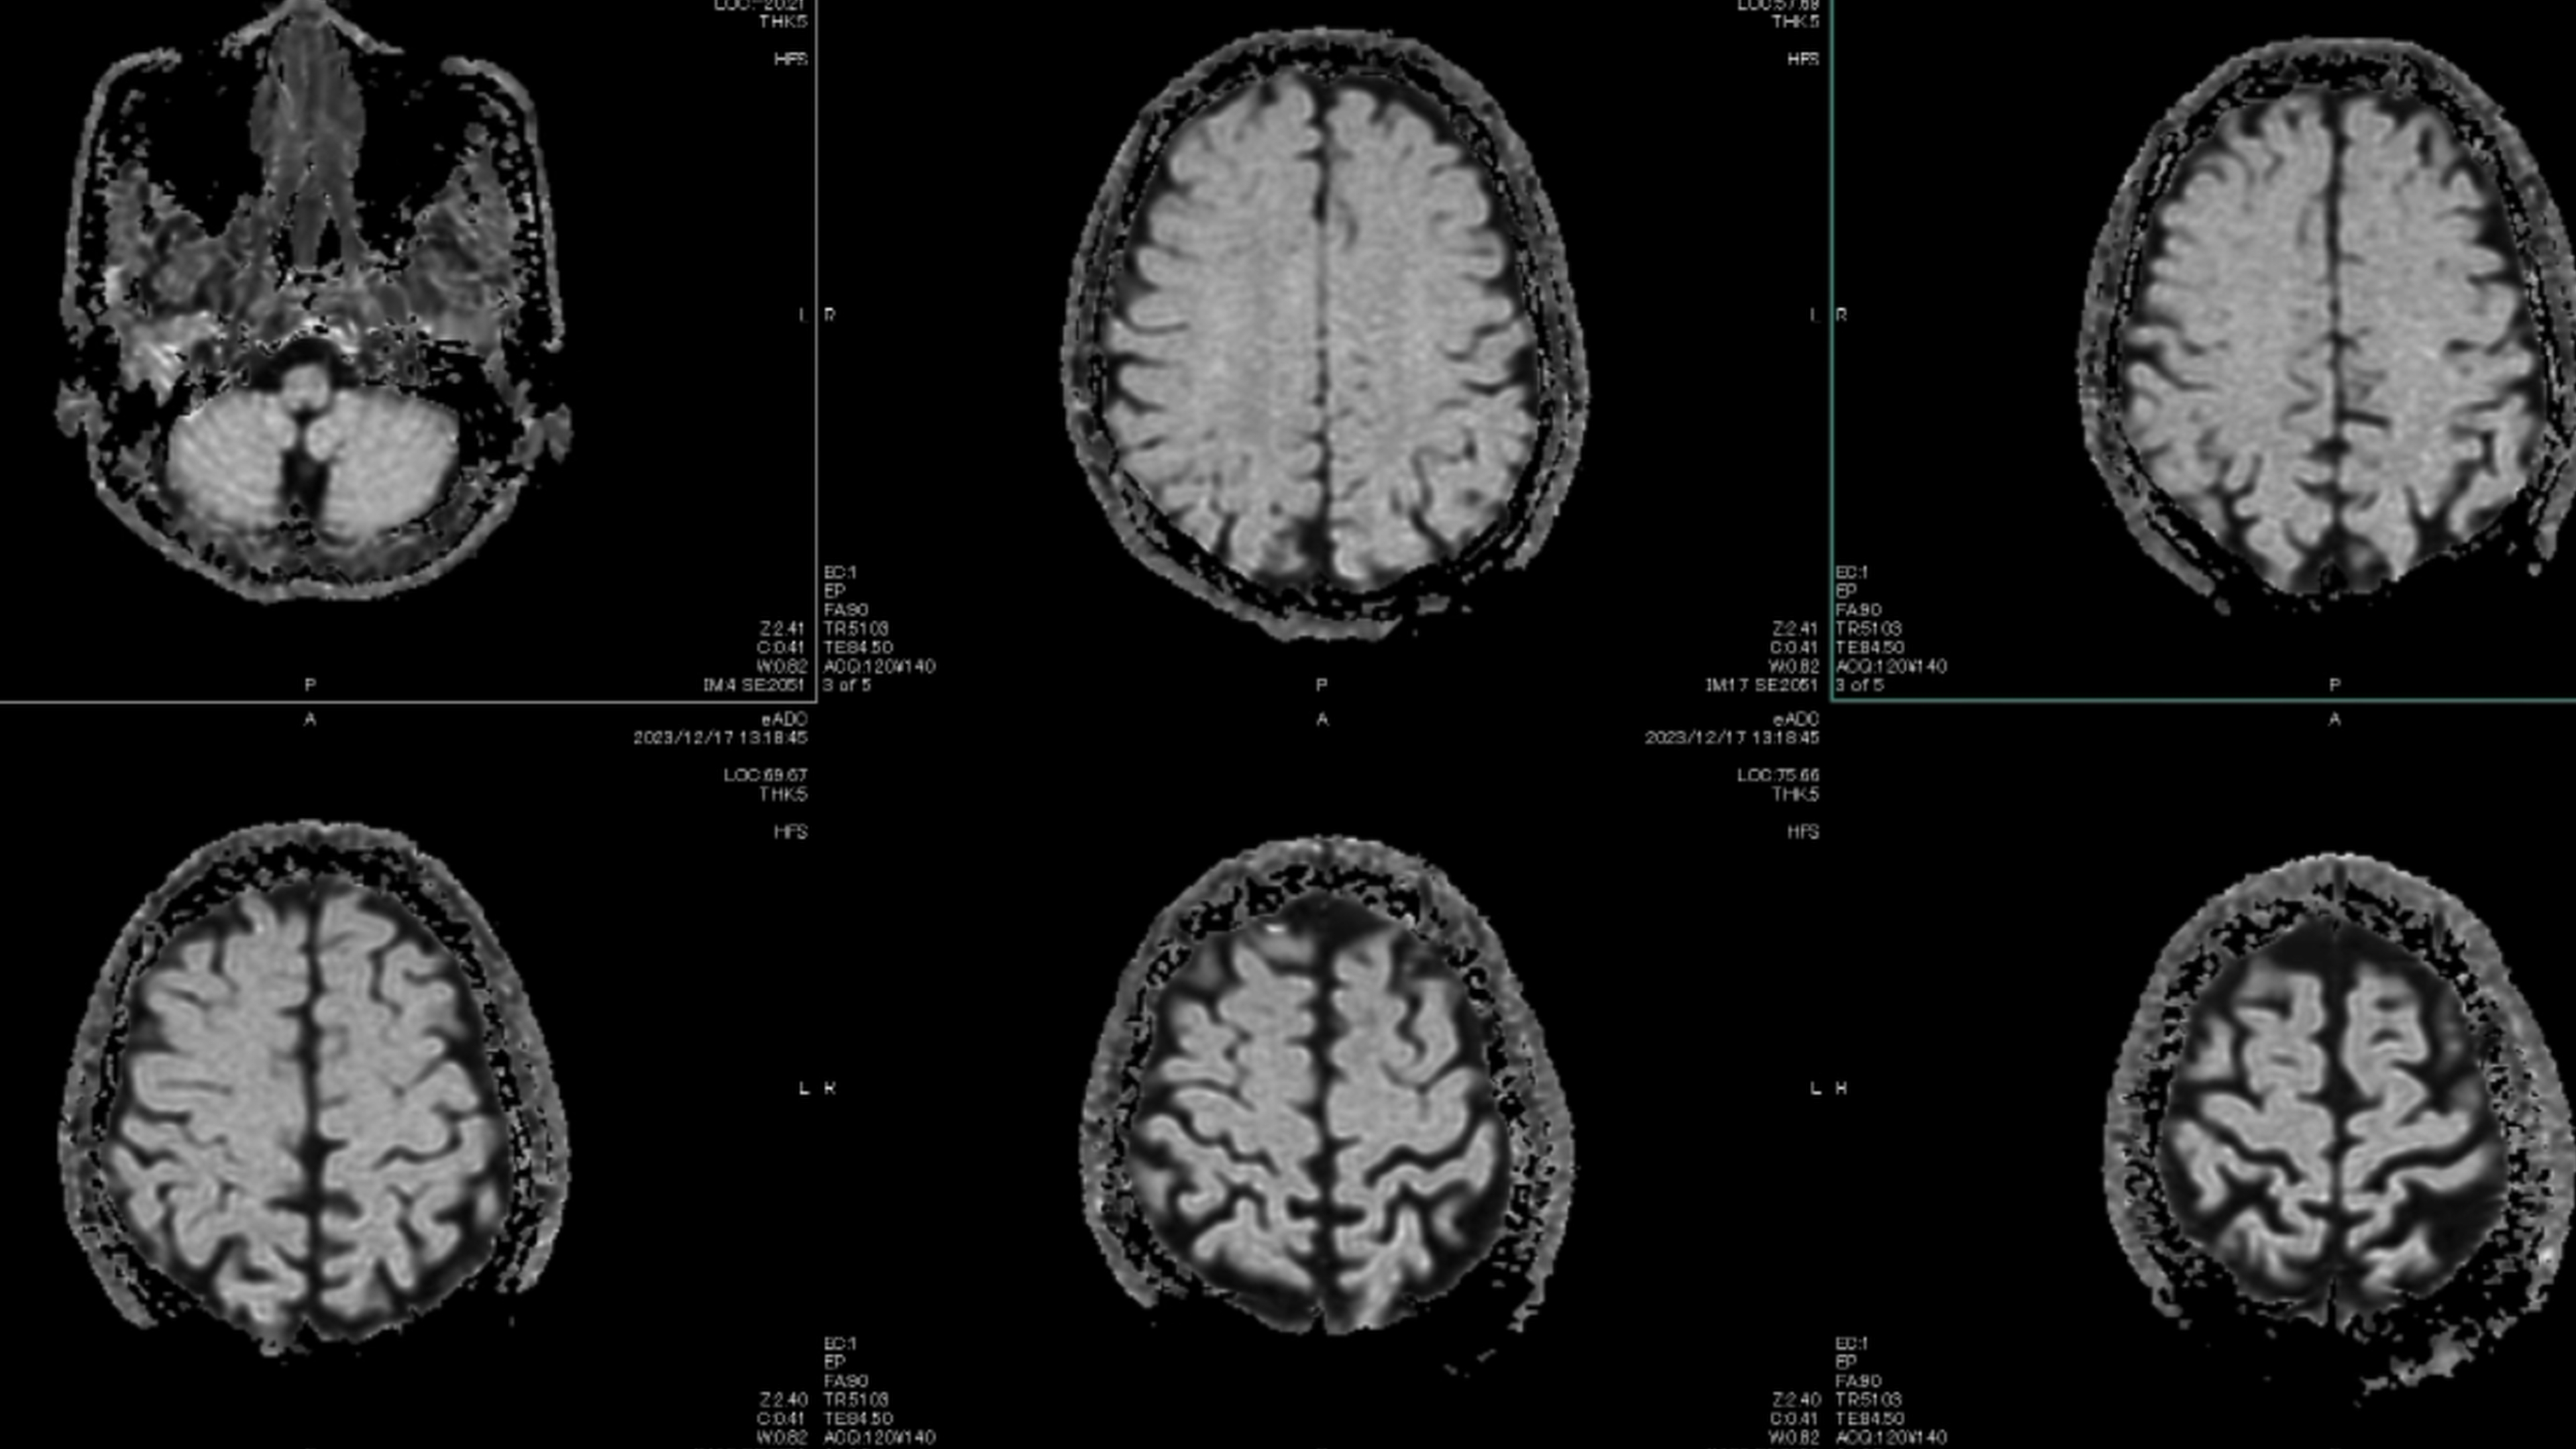

These are the best, creepiest, weirdest facts I have ever learned. "There's the part of your brain that recognizes faces, and the part that stores memories and feelings associated with a person. In a normally functioning brain, when you see a person you recognize, your brain looks up the feelings associated with that person. In Capgras, that process fails, so when you see someone you know and love, you get this strong sense that it just doesn't feel like that person. So your brain reconciles that disconnect by concluding that the person must be an imposter or duplicate. You can imagine the paranoia it would lead to if suddenly every important person in your life felt off, and you thought everyone was an alien clone or something." "So what the scientific community says, which makes reasonable sense, is that when the brain realizes when the heart stops, and oxygen levels plummet fast, the brain uses all of its last energy to look through all of its memories to try to make sense of this unprecedented catastrophic thing that’s happening to it." "When I had my near-death experience, I had the 'life flashing before my eyes' thing, but it wasn't like a video on fast-forward. It was a single emotional impression of the sum total of all my actions in life. It was pretty terrifying and caused me to change how I lived." "If that isn't enough to creep you out, the environment of the bog keeps much of their body preserved; hair, skin, and organs all kept intact, so the bodies have retained much of their original human form except for their bones. Which are dissolved. Look up pictures of a bog body; they are so fascinating. Creepy, too. Forensic anthropologists have even discovered remnants of a last meal in several of these bodies. I guess vegetable porridge and gruel were popular back in the day." "When we had the first countrywide outbreak here, my brother, who was dating a beef farmer, came home one day white as a sheet. He said he had just watched a cow literally break dance in front of him, then drop down and die. He was freaked out that something that big could move like that and then die in front of him. I doubt it was head spins, but I guess you try to describe something you have never seen before." Please note: some comments have been edited for length and/or clarity.